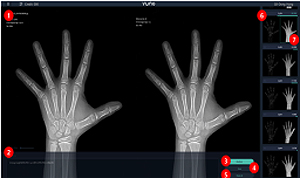

뷰노메드 본에이지는 AI가 엑스레이 영상을 분석해 환자 뼈 나이를 제시하고, 의사가 제시된 정보 등으로 성조숙증이나 저성장을 진단하는데 도움을 주는 역할을 한다.

그동안 의사가 환자의 왼쪽 손 엑스레이 영상을 참조표준영상(GP)과 비교하면서 수동으로 뼈 나이를 판독하던 것을 자동화해 판독시간을 단축한 것이 특징이다.

구체적으로 살펴보면, 인공지능이 촬영된 엑스레이 영상의 패턴을 인식해 성별(남자 31개, 여자 27개)로 분류된 뼈 나이 모델 참조표준영상에서 성별·나이별 패턴을 찾아 유사성을 확률로 표시하면 의사가 확률값, 호르몬 수치 등의 정보를 종합해 성조숙증이나 저성장을 진단한다.